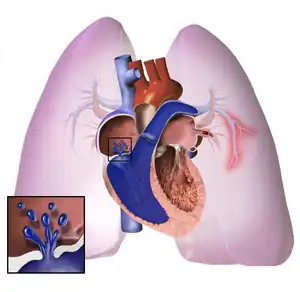

The pathogenesis of pulmonary arterial hypertension (WHO Group I) involves the narrowing of blood vessels connected to and within the lungs. This makes it harder for the heart to pump blood through the lungs, much as it is harder to make water flow through a narrow pipe as opposed to a wide one. Over time, the affected blood vessels become stiffer and thicker, in a process known as fibrosis. The mechanisms involved in this narrowing process include vasoconstriction, thrombosis, and vascular remodeling (excessive cellular proliferation, fibrosis, and reduced apoptosis/programmed cell death in the vessel walls, caused by inflammation, disordered metabolism and dysregulation of certain growth factors).[24][25] Over time, vascular remodeling causes the affected blood vessels to become progressively stiffer and thicker. This further increases the blood pressure within the lungs and impairs their blood flow. In common with other types of pulmonary hypertension, these changes result in an increased workload for the right side of the heart.[11][26] The right ventricle is normally part of a low pressure system, with systolic ventricular pressures that are lower than those that the left ventricle normally encounters. As such, the right ventricle cannot cope as well with higher pressures, and although right ventricular adaptations (hypertrophy and increased contractility of the heart muscle) initially help to preserve stroke volume, ultimately these compensatory mechanisms are insufficient; the right ventricular muscle cannot get enough oxygen to meet its needs and right heart failure follows.[11][25][26] As the blood flowing through the lungs decreases, the left side of the heart receives less blood. This blood may also carry less oxygen than normal. Therefore, it becomes harder and harder for the left side of the heart to pump to supply sufficient oxygen to the rest of the body, especially during physical activity.[27][28][19]

In PVOD (WHO Group 1'), pulmonary blood vessel narrowing occurs preferentially (though not exclusively) in post-capillary venous blood vessels.[29] PVOD shares several characteristics with PAH, but there are also some important differences, for example differences in prognosis and response to medical therapy.